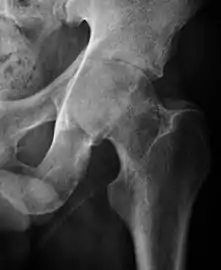

Projectional radiography ("X-ray") is the first imaging technique of choice in hip pain, not only in older people with suspected osteoarthritis but also in young people without any such suspicion. In this case plain radiography allows categorization as normal hip or dysplastic hip, or with impingement signs, pincer, cam, or a combination of both.[1]

X-Ray

Projectional radiography ("X-ray") is currently useful not only in older people in whom osteoarthritis of the hip is suspected but also in younger people without osteoarthritis, who are being evaluated for femoroacetabular impingement (FAI) or hip dysplasia.[1]

Plain radiography allows us to categorize the hip as normal or dysplastic or with impingement signs (pincer, cam, or a combination of both). Besides these, pathologic processes like osteoarthritis, inflammatory diseases, infection, or tumors can also be identified (Figure 1).[1]

Figure 1.

Radiography in normal hip

X-ray in pincer impingement type of hip dysplasia

X-ray of cam

Hip in osteoarthritis

Septic arthritis

X-ray in pediatrics